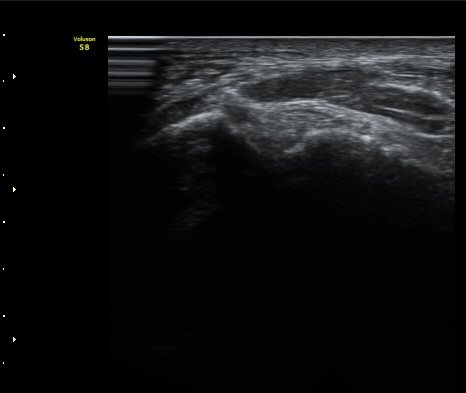

Àü°Å°ñºñ°ñÀδë Á¾´Ü¸é°Ë»ç»ó Àδë ÀδëÀÇ Àú¿¡ÄÚ ºÎÁ¾°ú(±×¸² 3)

ºñ°ñºÎÂøºÎ ¿¬°á¼º ¼Ò½ÇÀÌ °üÂûµÈ´Ù(±×¸² 4).

±×¸²3) Àü°Å°ñºñ°ñÀδë Á¾´Ü¸é°Ë»ç

±×¸²4) Àü°Å°ñºñ°ñÀδë Á¾´Ü¸é°Ë»ç